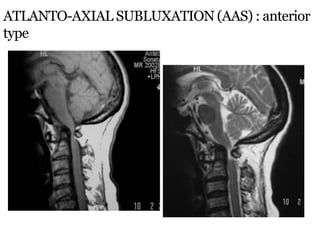

ATLANTO-AXIAL SUBLUXATION (AAS) : anterior

type

Anterior Atlanto-Dental Interval (AADI) :

 AAS is present when it is >3mm in adults & >5mm in

children

 Measured from posteroinferior margin of ant arch of C1

to the ant surface of odontoid

 AADI 3-6 mm  trans lig. damage

 AADI >6mm  alar lig. damage also

 AADI >9mm  surgical stabilization

ATLANTO-AXIAL SUBLUXATION (AAS) :

anterior type

Posterior Atlanto-Dental

Interval (PADI) :

** Distance b/w posterior

surface of odontoid &

anterior margin of post ring of

C1

 Considered better method as it

directly measures the spinal

canal

 Normal : 17-29 mm at C1

 PADI <14mm : predicts cord

compression